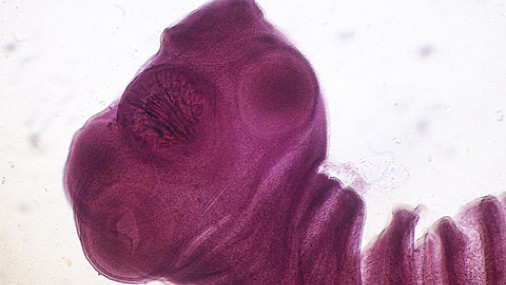

Taenia solium (tenia o verme solitario) e cisticercosi Admin LSWN [ultimo aggiornamento: 19/08/2018] La Taenia solium (detta anche tenia o verme solitario) è un verme parassita che appartiene alla... 19 dicembre 2005